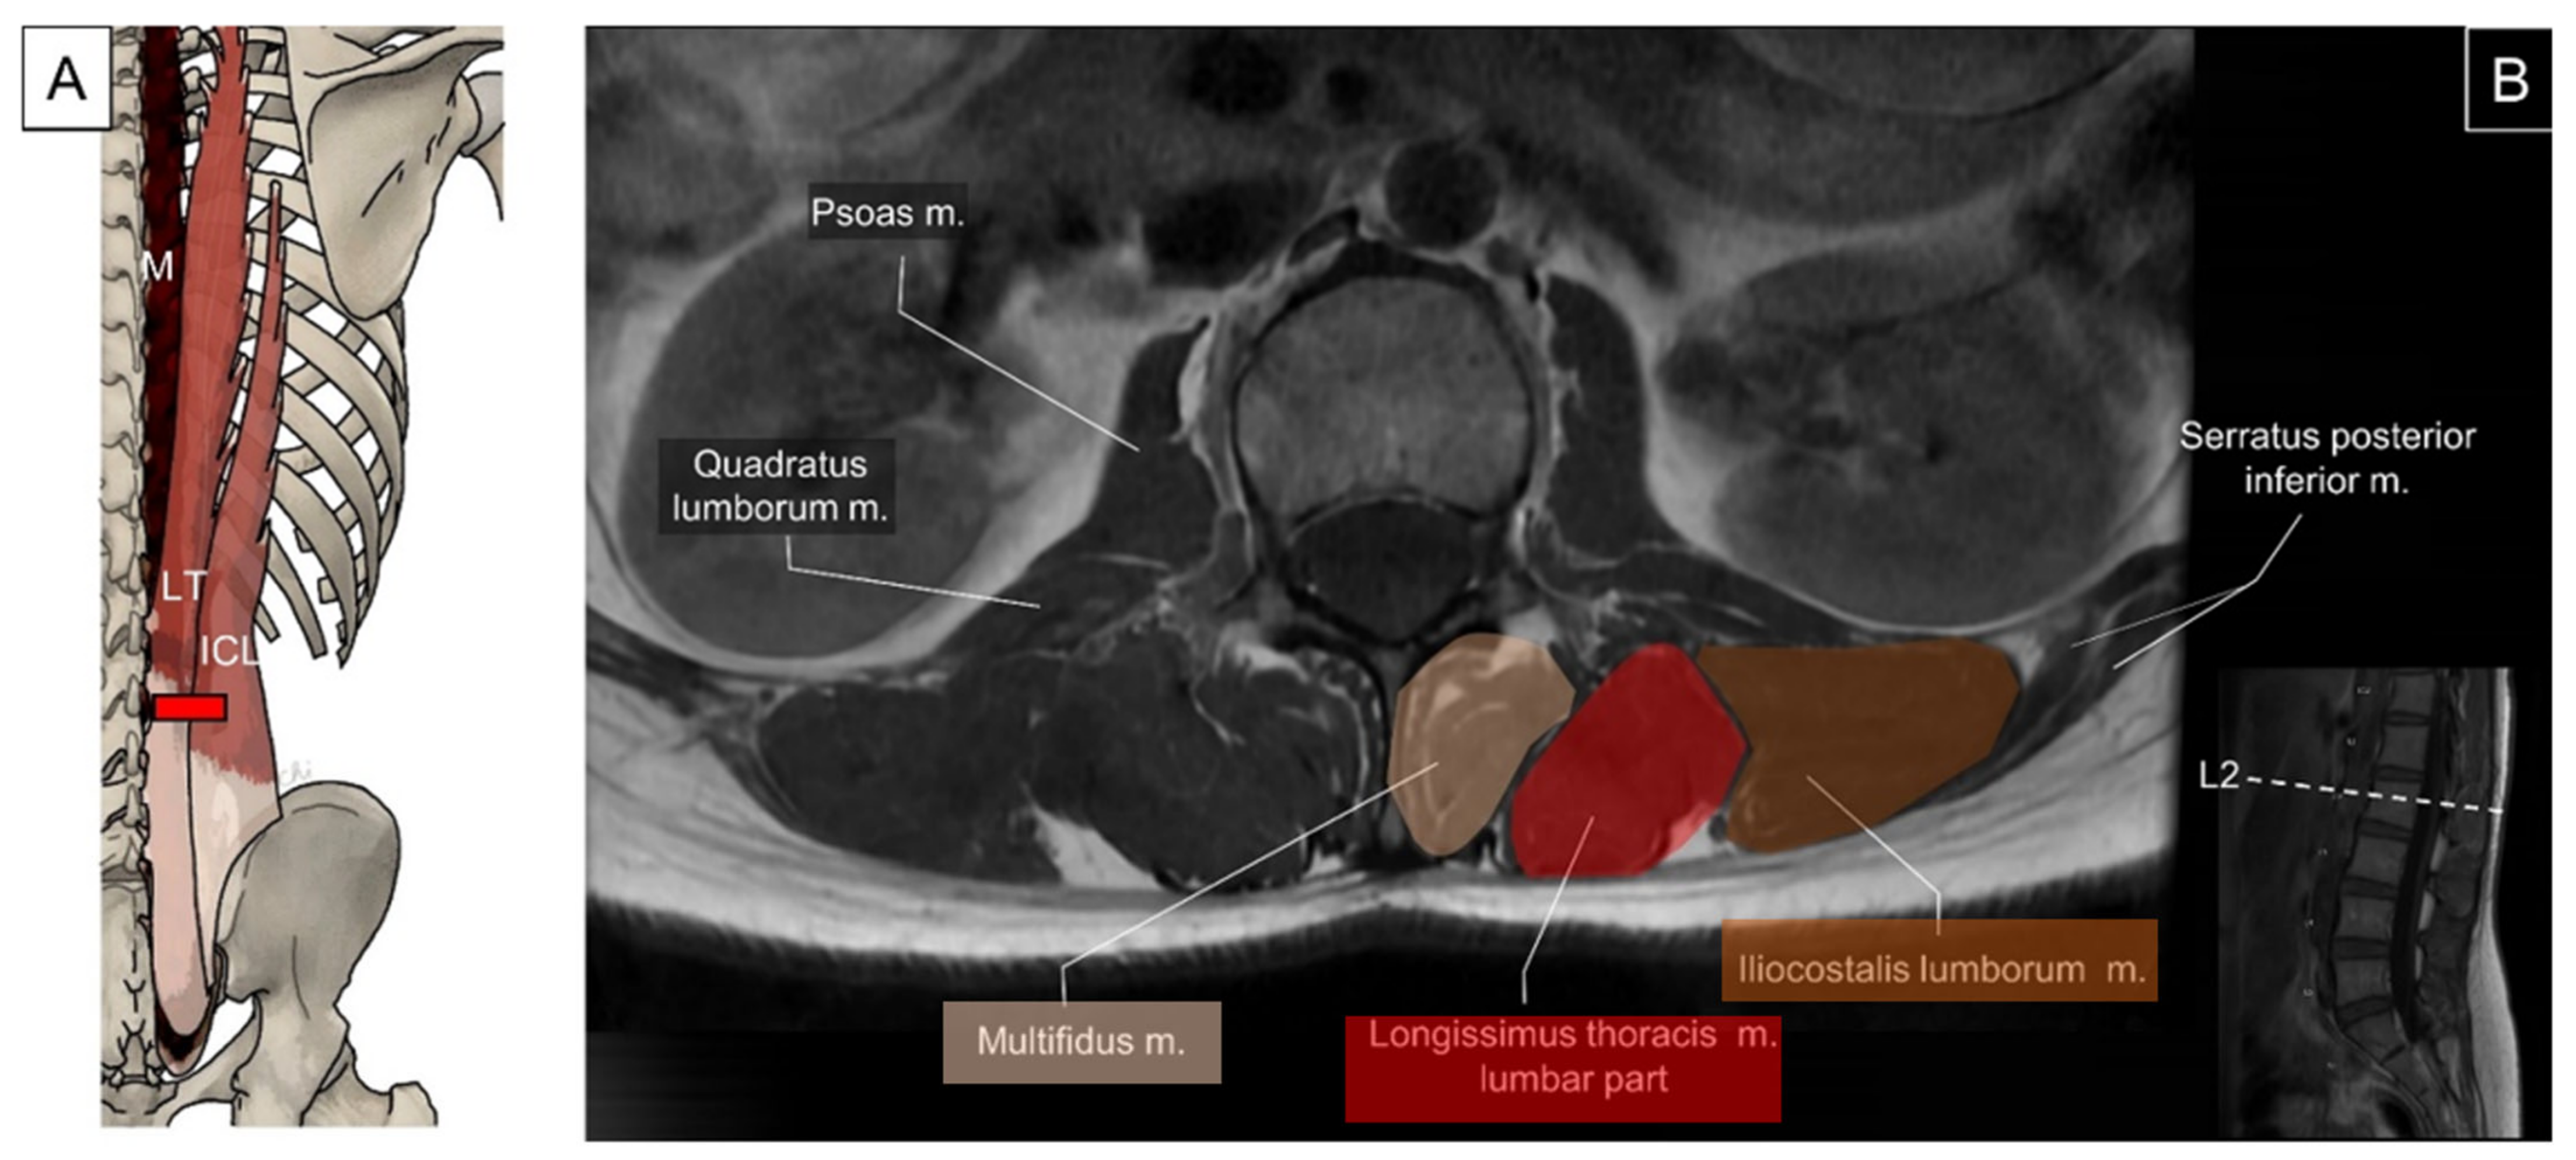

5.2.1. Anatomy

5.2.2. Sonographic Scanning

5.2.3. Clinical Relevance